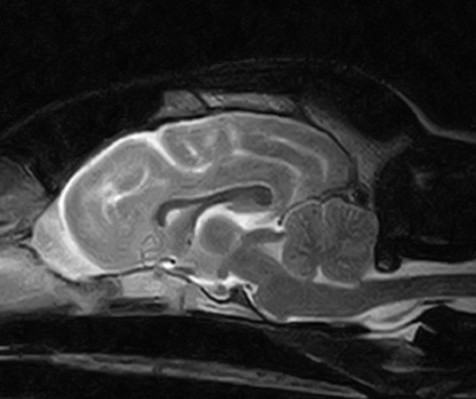

神経内科

神経外科